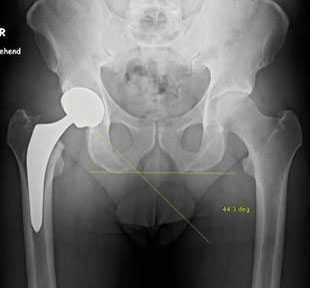

Рис.: рентгенограмма прогрессирующих дистрофических изменений правого тазобедренного сустава

Рис.: Бесцементный тотальный эндопротез правого тазобедренного сустава, установленный в результате малоинвазивной операции по AMIS-технологии.

Бесцементный тотальный эндопротез правого тазобедренного сустава, установленный в результате малоинвазивной операции по AMIS-технологии.